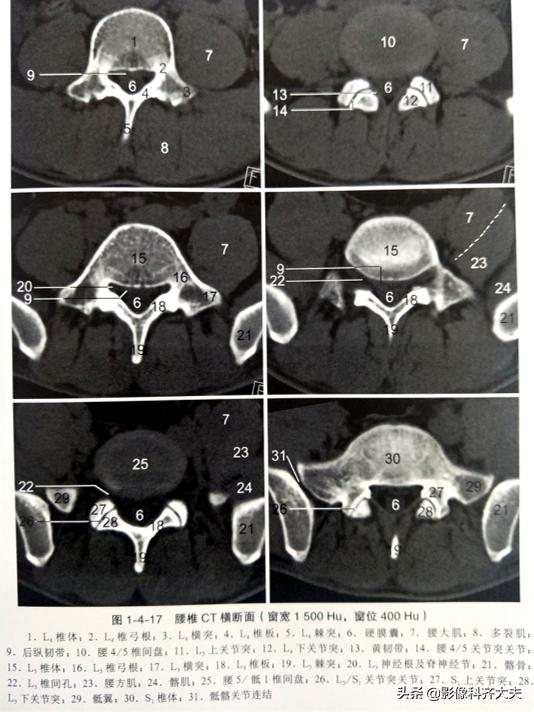

CT及MRI表现:

①正常腰椎间盘后缘不超过椎体骨性终板的后缘,且中部略有凹陷呈肾形。椎间盘脱出表现为局部突出于椎体后缘的弧形软组织影,通常与椎间盘相连,且密度多一致,并可见硬脊膜外游离髓核。髓核在椎间盘平面上方或下方,其密度低于椎骨但高于硬脊膜及椎旁软组织,突出的椎间盘可钙化。

②硬脊膜外脂肪受压、移位,甚至消失,硬脊膜下腔前缘或侧方受压变形。

③向侧后方突出的椎间盘,可使侧隐窝前、后径缩短,压迫相应的脊神经根使其向后移位;脊神经根亦可因水肿而增粗。

④椎体后部骨质硬化及有时可见椎间相邻椎体上、下缘可见许莫氏(Schmorl)结节。

椎间盘膨出CT及MRI表现:

①轻度膨出时表现为椎间盘后缘正常肾形凹陷消失,圆隆饱满。

②重度时弥漫膨出的间盘边缘明显向四周均匀一致增宽,超出上下椎体边缘,但椎间盘仍然对称,没有局部突出,外形保持椭圆形,可伴真空变性。严重时可造成硬膜囊受压狭窄,马尾神经受压。

CT椎间盘突出分型

以椎间盘疝出物突出的方向分为四型,即中央型、外侧型、远外侧型和侧前型。

前两种为椎管内型,后两种为椎管外型。

中央型椎间盘疝出物位于椎管中部主要对硬膜外脂肪间隙和硬膜囊形成压迫;

外侧型椎间盘疝出物位于椎管内一侧,未超过椎间孔内口,主要对硬膜外脂肪间隙、硬膜囊和神经根形成压迫;

远外侧型椎间盘疝出物位于椎管以外,主要引起椎间孔狭窄和一侧根神经受压;

侧前型椎间盘疝出物本身不引起压迫症状,但由于椎间盘的外1/3有神经分布,亦是腰痛的原因之一,所以应引起足够的重视。

椎间盘突出程度与椎管狭窄程度并不呈正比,椎管狭窄程度受疝出物大小、硬膜囊大小、韧带厚度、关节肥大和椎间盘膨出等因素的影响。

CT:椎间盘突出(中央型)